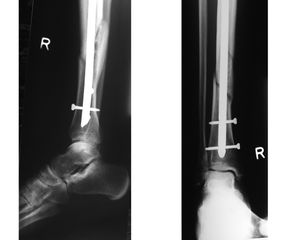

كسر العظام

كسر العظام Fracture، هي حالة طبية يكون فيها كسر في اتصال العظم. وقد يكون كسر العظام نتيجة ارتطام أو ضغط قوة كبيرة، أو اصابة بسيطة نتيجة حالات طبية معينة تضعف العظام، مثل هشاشة العظام، سرطان العظم، أو osteogenesis imperfecta، حيث يسمى الكسر بالكسر الپاثولوجي. هناك عدة أنواع من الكسور؛ والأنواع الشائعة هي، الكسر البسيط، والكسر المركب، والكسر المضاعف، والكسر المفتَّت، وكسر العصا الخضراء، والكسر اللولبي. تنكسر عظام الناس من مختلف الأعمار. غير أن عظام الأشخاص كبار السن تكون أهش من عظام الشباب. فعظام كبار السن تنكسر بسهولة أكبر وتحتاج إلى وقت أطول كي تلتئم.

- كسر مركب: وفيه تنكسر العظمة ويتمزق الجلد الذي فوقها.